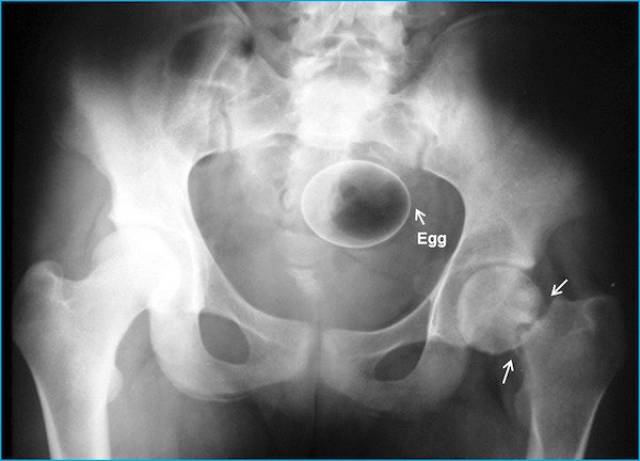

An egg (obviously).